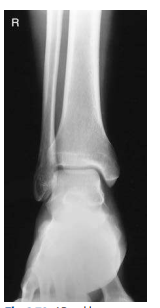

What ankle view is this?

AP